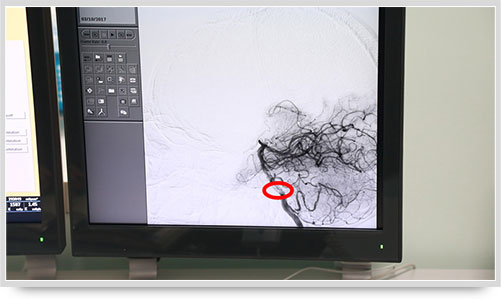

病变血管一目了然

45岁的朱姓患者因“多发性腔性脑梗塞”头晕不明,接受了全脑血管造影术,术中显示他的颅内椎动脉血管痉挛(红圈内为病变部位)。据李主任介绍,以前像脑梗塞等脑血管疾病只能被定位到脑的功能区域,无法确定责任血管,而实施全脑血管造影术就能精准地找出病变血管,好比揪出了造成脑梗塞的“祸首”,大大提高了脑血管疾病的诊治水平。

之前,另一位61岁的李姓脑出血患者,康复治疗半个月后复查,也接受了全脑血管造影术,术中显示大脑前动脉A1段动脉瘤(不同维度显影,红圈内为动脉瘤瘤体)。像这样的病人,必须进一步进行手术治疗,及早清除动脉瘤,避免因瘤体破裂造成再次出血危及生命。